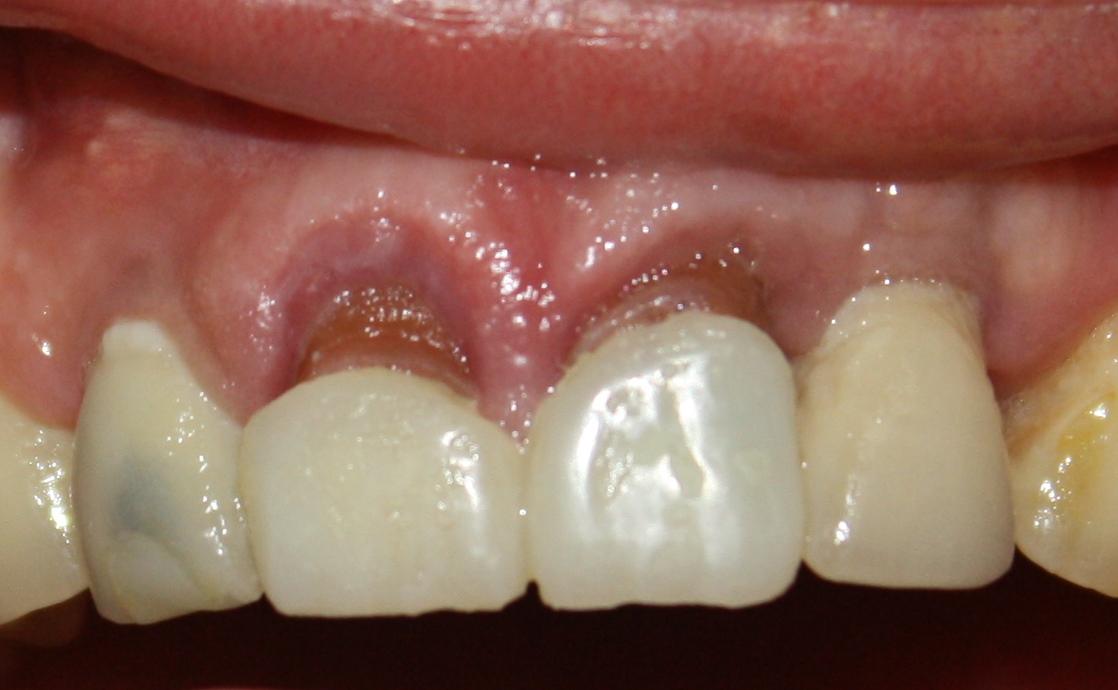

Около трёх лет назад к нам в клинику обратилась пациентка Мария, на момент обращения ей было 45 лет. Её беспокоила ситуация с передними резцами:

В ходе беседы она рассказала, что лечит эти зубы всю сознательную жизнь — их депульпировали («удалили нерв») из-за последствий травмы еще в школьном возрасте, и после этого каждые несколько лет (а то и чаще) ей приходилось перелечивать каналы, менять коронки, вкладки и т. д.

В результате, зубы приобрели очень уж нездоровый вид (см. фото выше). Вдобавок, всё усугубилось существенным снижением качества жизни — коронки и вкладки из зубов постоянно выпадают, десна вокруг них кровоточит при чистке…. Кроме того, Марию не покидает ощущение того, что эти зубы могут просто вывалиться в самый неподходящий момент. Именно это заставило её обратиться в нашу клинику.

Визуальный осмотр:

Подвижность зубов (или коронок) II-III степени косвенно свидетельствует о разрушении периодонтальных связок и стенок лунок зубов. Подвижность является следствием хронического воспаления, когда окружающие зуб ткани остаются без питания и деградируют — и в совокупности это может существенно осложнить сохранение эстетических параметров окружающих имплантат тканей. Степень риска — высокая.

Слизистая оболочка в области центральных резцов отёчна, при прикосновении кровоточит — прямое следствие хронического воспаления. Пока слизистая оболочка воспалена, она не способна к регенерации. Это значит, что операционные раны на такой слизистой вряд ли будут нормально заживать. Степень риска — высокая.

Рецессия десны из-за хронического воспаления — признак запущенного длительного существующего воспалительного процесса, в результате которого разрушается, в том числе, костная ткань. В таких условиях её регенеративная способность, не говоря уже свойствах десны, существенно снижается. Скорее всего, на КЛКТ мы увидим утрату вестибулярной стенки лунки (что объясняет подвижность). Степень риска — высокая.